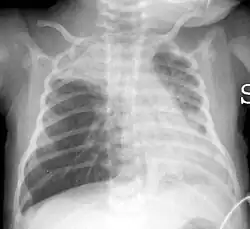

Najczęstsze objawy ostrego zapalenia oskrzelików to przyspieszone oddychanie (tachypnoe) i wydłużenie wydechu. W badaniu przedmiotowym podczas osłuchiwania płuc stetoskopem stwierdza się świsty. W badaniu rentgenowskim płuc widoczne są zmiany o charakterze rozdęcia płuc, zagęszczenia pęcherzykowe (wywołane wypełnieniem pęcherzyków płucnych przez płyn[4]), zacienienia o charakterze guzków, siateczkowate. W spirometrii obserwuje się cechy obturacji oskrzeli. W badaniu histopatologicznym tkanki płucnej stwierdza się zmiany obrzękowe i martwicze w obrębie nabłonka oskrzelików. Wnętrze oskrzelików może być wypełnione wysiękiem i śluzem.